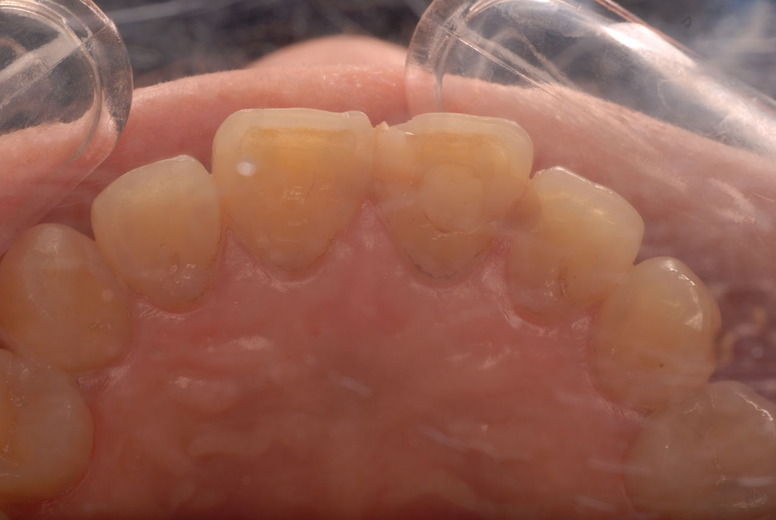

歯周病の疑いで東京のかなり遠方の方が来院されました。

驚くべきことですが、定期検診は受けていたそうです。しかしながら歯周病の指摘は受けたことがないそうです。

何故か?定期検診が虫歯のチェックのみになり、又肝心の歯周病の検査や歯周病の部分の予防や治療のためのブラシの使い方などを学んだ事がないのです。

本当に患者さんのことを考えると憂鬱になります。歯周病が悪化すると殆ど回復は無理だからです。